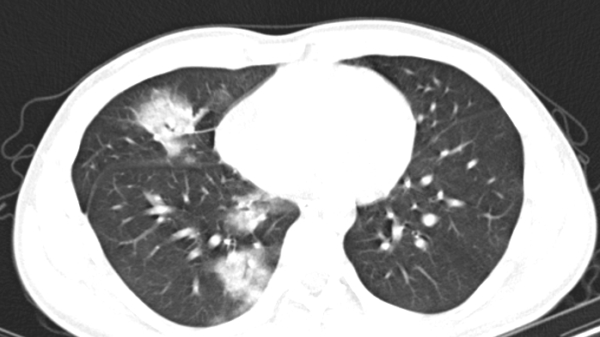

Nhập viện điều trị viêm phổi nặng các bác sĩ Bệnh viện Nhi đồng Thành phố (TP.HCM) cấp cứu bằng kỹ thuật trao đổi oxy màng ngoài cơ thể - ECMO.